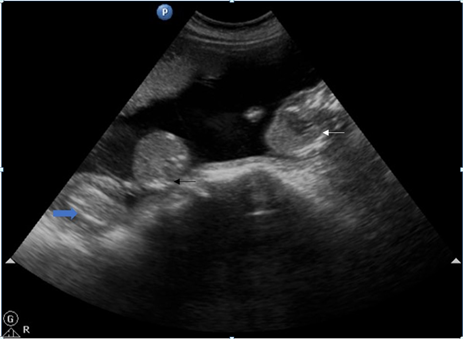

Figure 6 Trans-abdominal USG shows abnormal acardiac fetus with normal pumping twin and part of umbilical cords of both twins separately.

Figure 7 Post-delivery image of exencephaly fetus (white arrow), abnormal a cardiac mass (black arrow) and normal pumping fetus from left to right (blue arrow). All three umbilical cords are separately visualized (star).